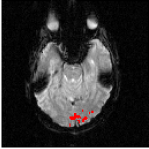

The Experience Based Cognition competition (EBC) (University of Pittsburgh, 2007) offers an opportunity to study complex responses to natural environments. The EBC datasets comprise three 20-minute runs (704 TRs in each run) of subjects interacting in an urban virtual reality environment. Subjects were audibly instructed to complete three search tasks in the environment: looking for weapons (but not tools) taking pictures of people with piercing (but not others), or picking up fruits (but not vegetables). The data was collected with a 3T EPI scanner (TR = s, xy dimension: , voxel size = mm, 34 slices with a thickness of mm). We analyze the second runs of subjects 14 and 13. For each subject, the matrix is composed of intra-cranial voxels at TRs. We first remove the non regionally specific variance captured by the first eigenmodes of a singular value decomposition of the dataset. We then compute using and . After embedding the dataset into four dimensions, we cluster the voxels. Figs. 18 and 20 display the datasets after embedding. Because we cannot display four dimensions, we show the projections of the dataset on three consecutive coordinates. All the coordinates contribute to the spread the dataset along elongated arms, which facilitates the clustering. Voxels that do not correspond to the background activity (the maroon cluster in Figs. 18 and 20) are superimposed on anatomically registered structural images and colored according to their cluster label (see Figs. 19 and 21). For both subjects, the clusters are connected regions (see Figs. 19 and 21), compactly organized around functional areas related to the processing of visual, and auditory stimuli (music, cellphone ringing, dog roaring) in the virtual environment. It is important to emphasize that our method never enforces any form of spatial proximity, and is purely based on functional connectivity.

For subject 14 (Fig. 19), the orange cluster corresponds to activation in the calcarine cortex associated with V1/V2 representations of the lower visual fields, while the light blue cluster corresponds to representations of the upper visual fields. Activation in lateral areas (visual motion areas, MT/V5) is also present, as well as activity in the posterior convexial cortex (area VP). The activation is predominantly in the right hemisphere. Interestingly, the two clusters located in the visual cortex (light blue and orange) have very similar and coordinates (see Fig. 18-left). The cyan cluster corresponds to activation in the right frontal gyrus (Broca area) associated with language comprehension. The yellow clusters are located in the right and left superior temporal gyri and medial temporal gyri (Wernicke area). These regions correlate with activation